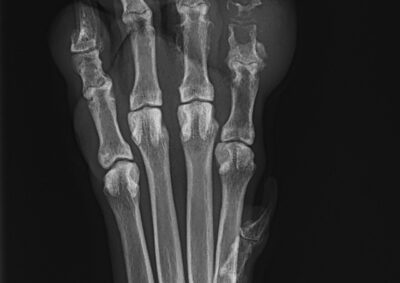

腫瘍外科 注意 ボタンをクリックした先に、治療中および手術中の画像が説明で使用されている場合がございます。 そのような画像に弱い方は閲覧なさらないようお願いいたします。 腫瘍外科 肝葉切除術 腫瘍外科 健康診断で発見された犬の甲状腺腫瘍 腫瘍外科 爪床腫瘍(扁平上皮癌) 腫瘍外科 肝葉切除(内側左葉) 救急・集中治療腫瘍外科 犬の巨大乳腺腫瘍 腫瘍外科 頭部肥満細胞腫 腫瘍外科 半側骨盤切除術 Hemi-Pelvectomy 腫瘍外科 Total Hemi-Pelvectomy 半側骨盤切除術 腫瘍外科 胃腺癌 胃部分切除 軟部組織外科腫瘍外科 両側甲状腺腫瘤切除、甲状腺濾胞腺癌 軟部組織外科腫瘍外科 右下顎骨切除 下顎悪性黒色腫 軟部組織外科腫瘍外科 肛門嚢アポクリン腺癌 右肛門嚢腫瘤 腰下リンパ節切除 <1234567> 症例カテゴリー 放射線治療整形外科軟部組織外科脳神経外科内科腫瘍外科救急・集中治療リハビリテーション科腫瘍内科内視鏡科脳神経科呼吸器外科中医・漢方猫の腎移植循環器科